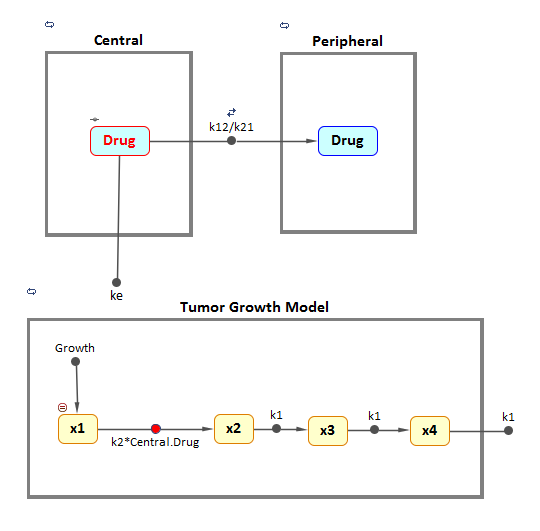

In 2004, Simeoni et al [1] proposed a PK/PD model to quantify the effect of anticancer drugs on tumor growth kinetics from in vivo animal studies. The drug pharmacokinetics were described by a 2-compartment model with bolus IV dosing and linear elimination (ke) from the Central compartment. Tumor growth was described as a biphasic process with an initial exponential growth followed by linear growth. The growth rate of the proliferating tumor cells, x1, was described by:

x1 is the weight of the proliferating tumor cells, and w is the total tumor weight. In the absence of drug, tumor is comprised only of proliferating cells, i.e. w=x1 . In the presence of an anticancer agent, it was assumed that a fraction of the proliferating cells were transformed into non-proliferating cells. The rate of this transformation was assumed to be a function of the plasma drug concentration and an efficacy factor, k2 . The non-proliferating cells, x2 , go through a series of transit stages ( x3 and x4 ) and are eventually cleared from the system. The transit stages were added to incorporate delay between the addition of the drug and observable reduction of tumor weight. Flow through the transit compartments was modeled as a first order process ( k1 ).